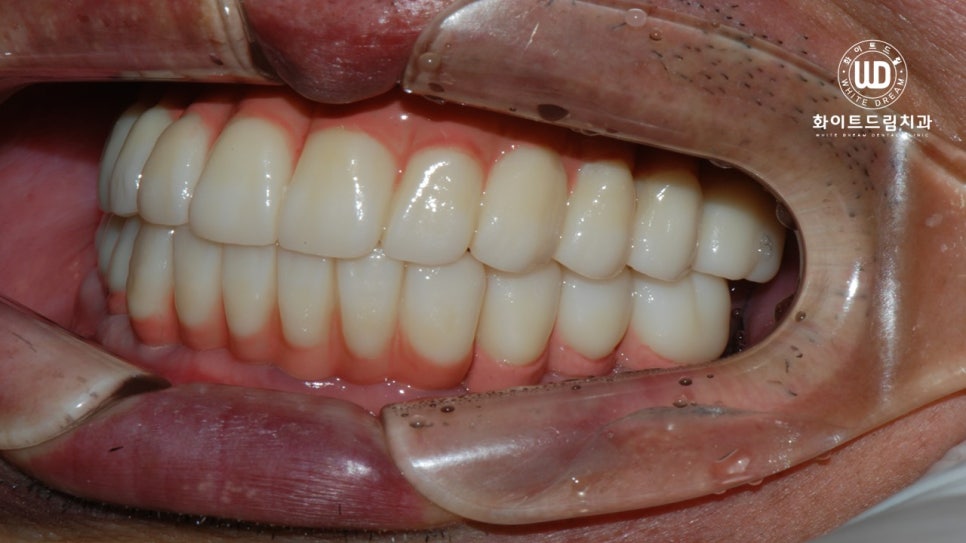

마지막으로, 하악 잔존 치아 2개 발치 후, 상하 전체 치조골 이식을 동반한 임플란트 식립 후 최종 진단 결과물입니다.

심미적, 기능적으로 주변 치아와 자연스럽게, 그리고 나이에 어울리도록 임플란트 시술이 마무리 된 것을 확인할 수 있었습니다.

진료 마무리 후 현재까지 부작용은 없는지, 치아 탈락 현상은 없는지 등 정기적인 검진을 진행해 드리고 있습니다.

뼈이식과 임플란트 식립에 있어서 가장 중요한 포인트는 바로 고정력 입니다. 임플란트를 여러개 식립하여 보철치료를 진행할 때, 저작하는 위치가 변하지 않고 모든 치아가 긴밀하게 위치할 수 있도록 교합 조절을 해드리는 것이 중요합니다.